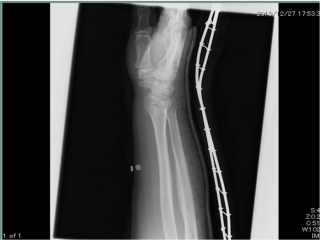

H25.12.26 60歳男性 橈骨遠位部骨折

橈骨遠位部骨折

スロープを降りていて転倒、手を衝き受傷。

提携医にてX-p検査後、確定診断をいただき

整復後、オルフィットエコ、シャーレにて固定。

受傷後(正面)

受傷後(側面)

整復後(正面)

整復後(側面)